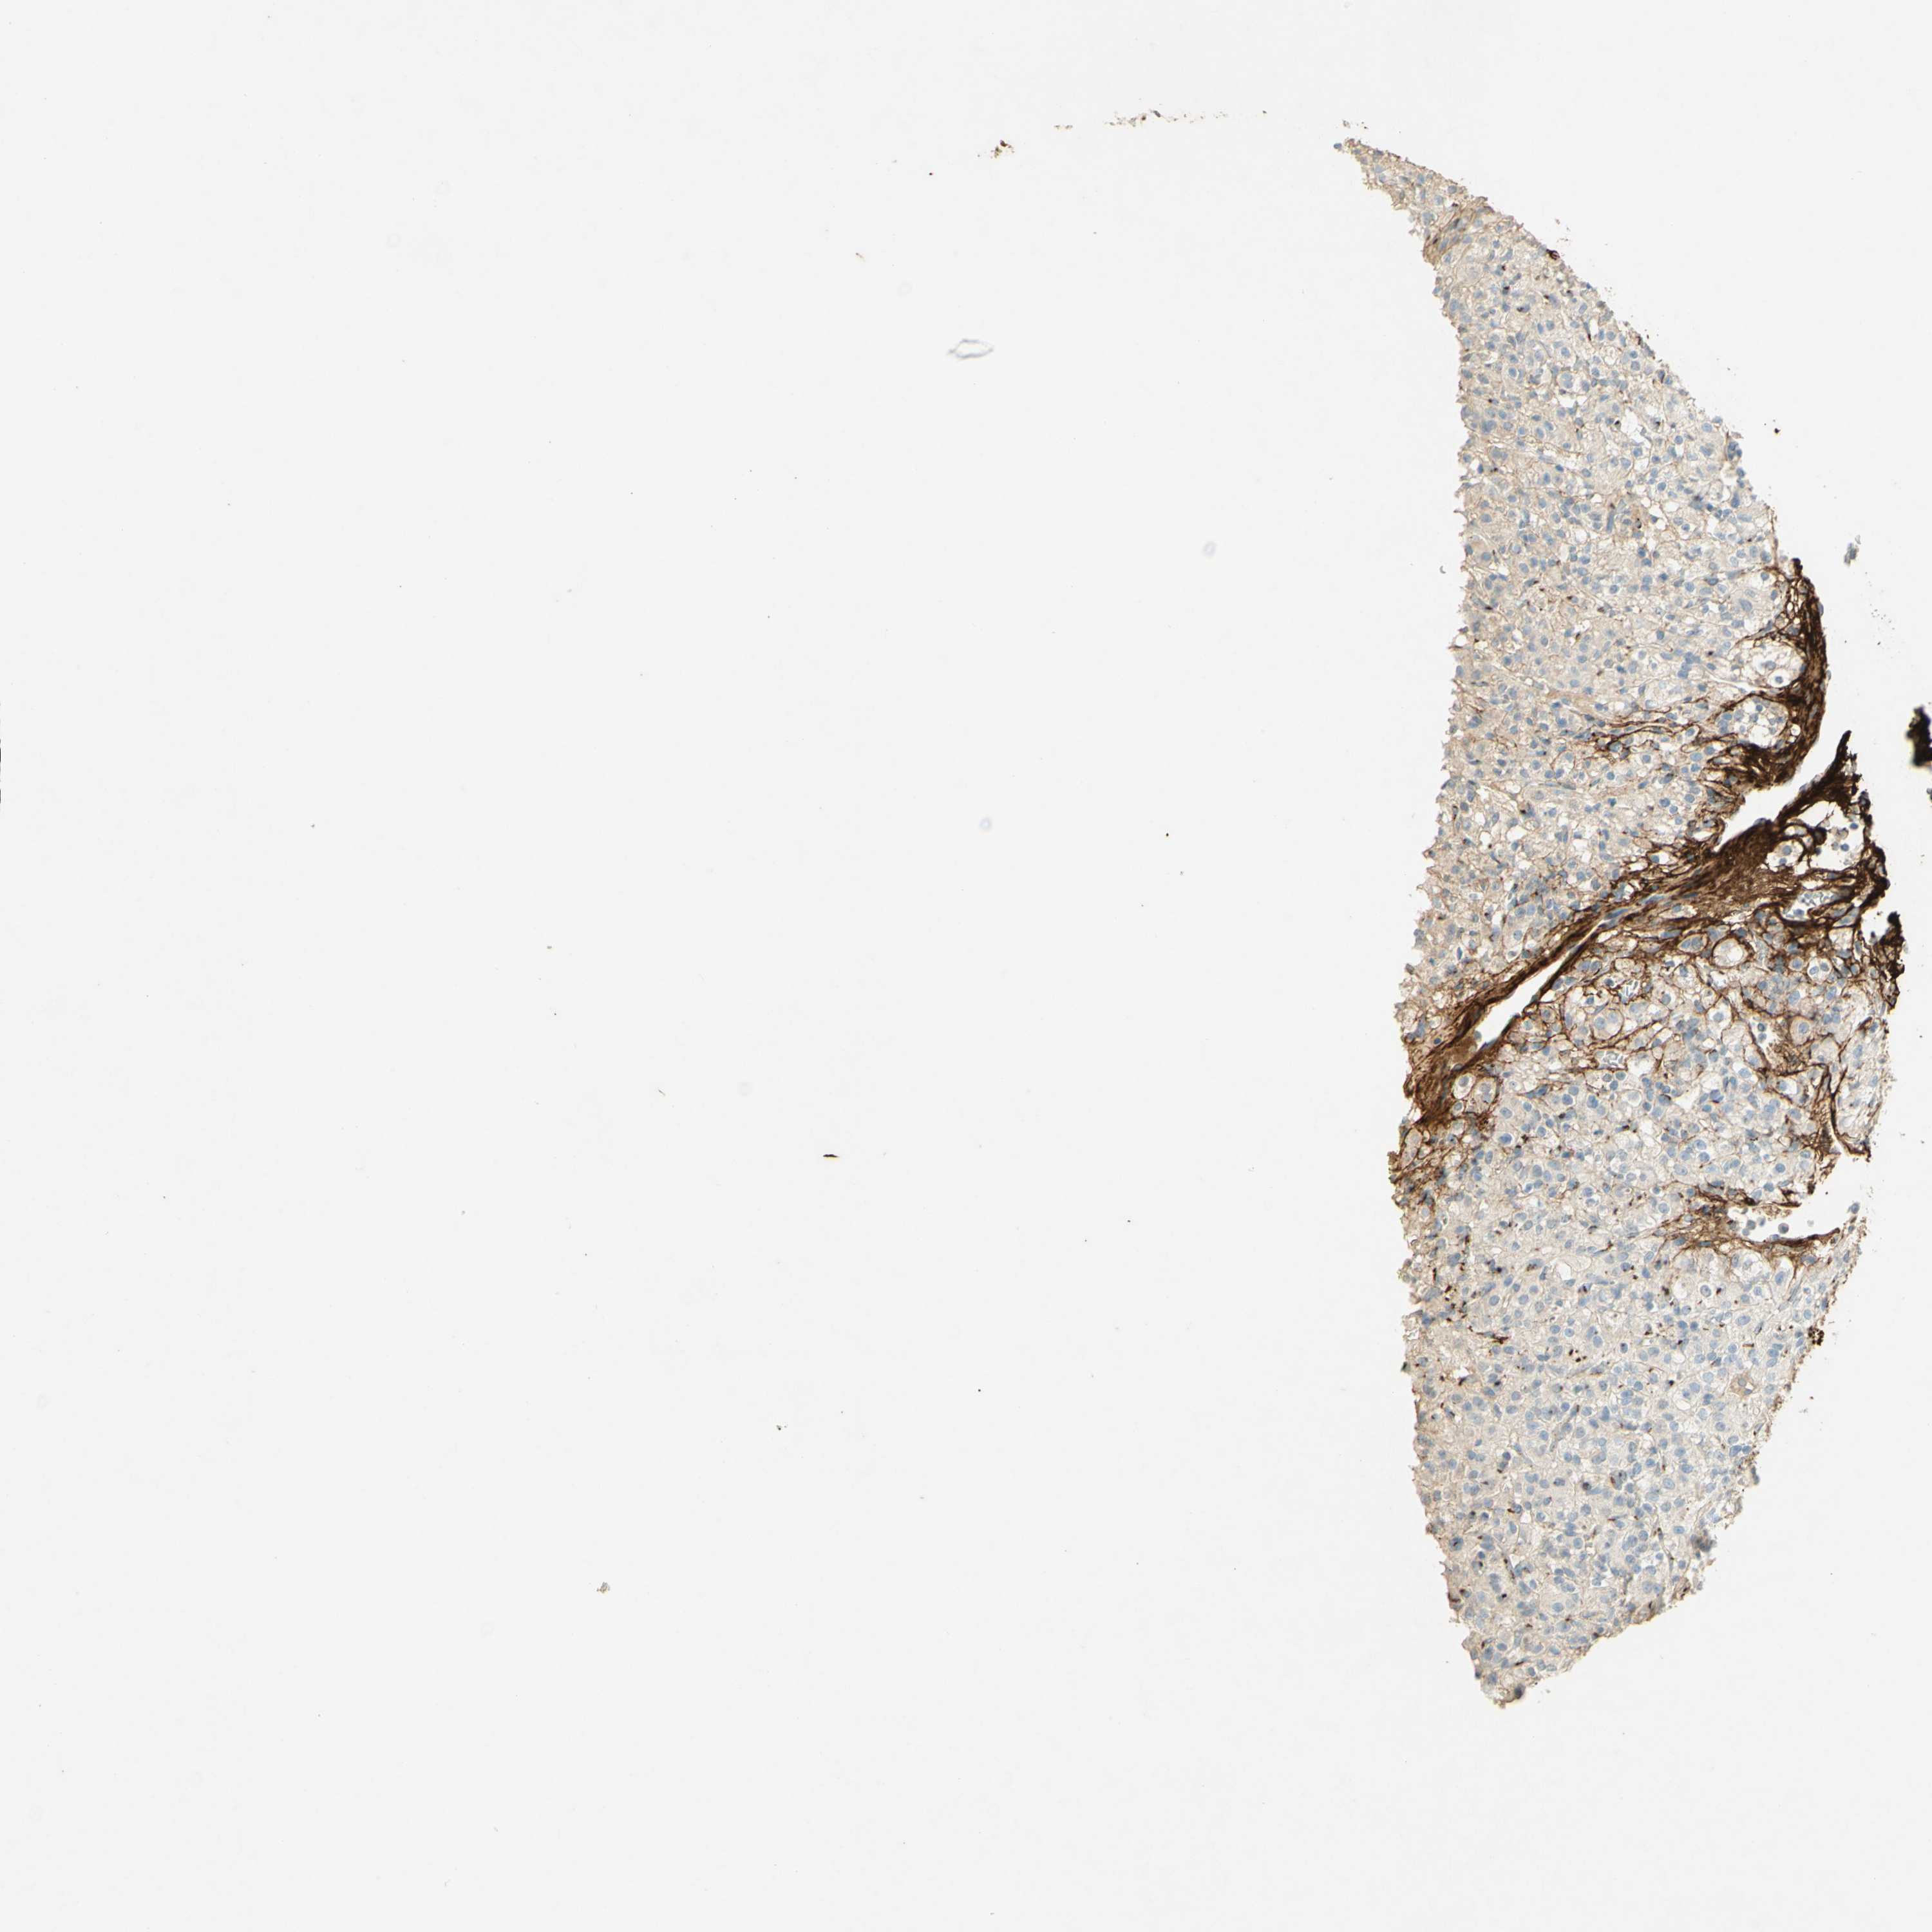

TCGA RNA samplesi

RNA-seq data is reported as average FPKM (number Fragments Per Kilobase of exon per Million reads), generated by the The Cancer Genome Atlas (TCGA) .

Normal distribution across the dataset is visualized with box plots, shown as median and 25th and 75th percentiles. Points are displayed as outliers if they are above or below 1.5 times the interquartile range. FPKM values of the individual samples are presented next to the box plot.

Average pTPM 0.3

Number of samples 100